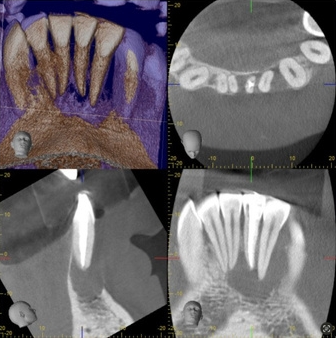

CBCT summary of tooth 31:

- Large periapical radiolucency measuring 12.4mm at the widest width.

- Perforation of buccal bone

- Lesion involving apex of 32 and 41 (adjacent teeth)

- CBCT was taken to examine the dimension of the lesion and surrounding structures.